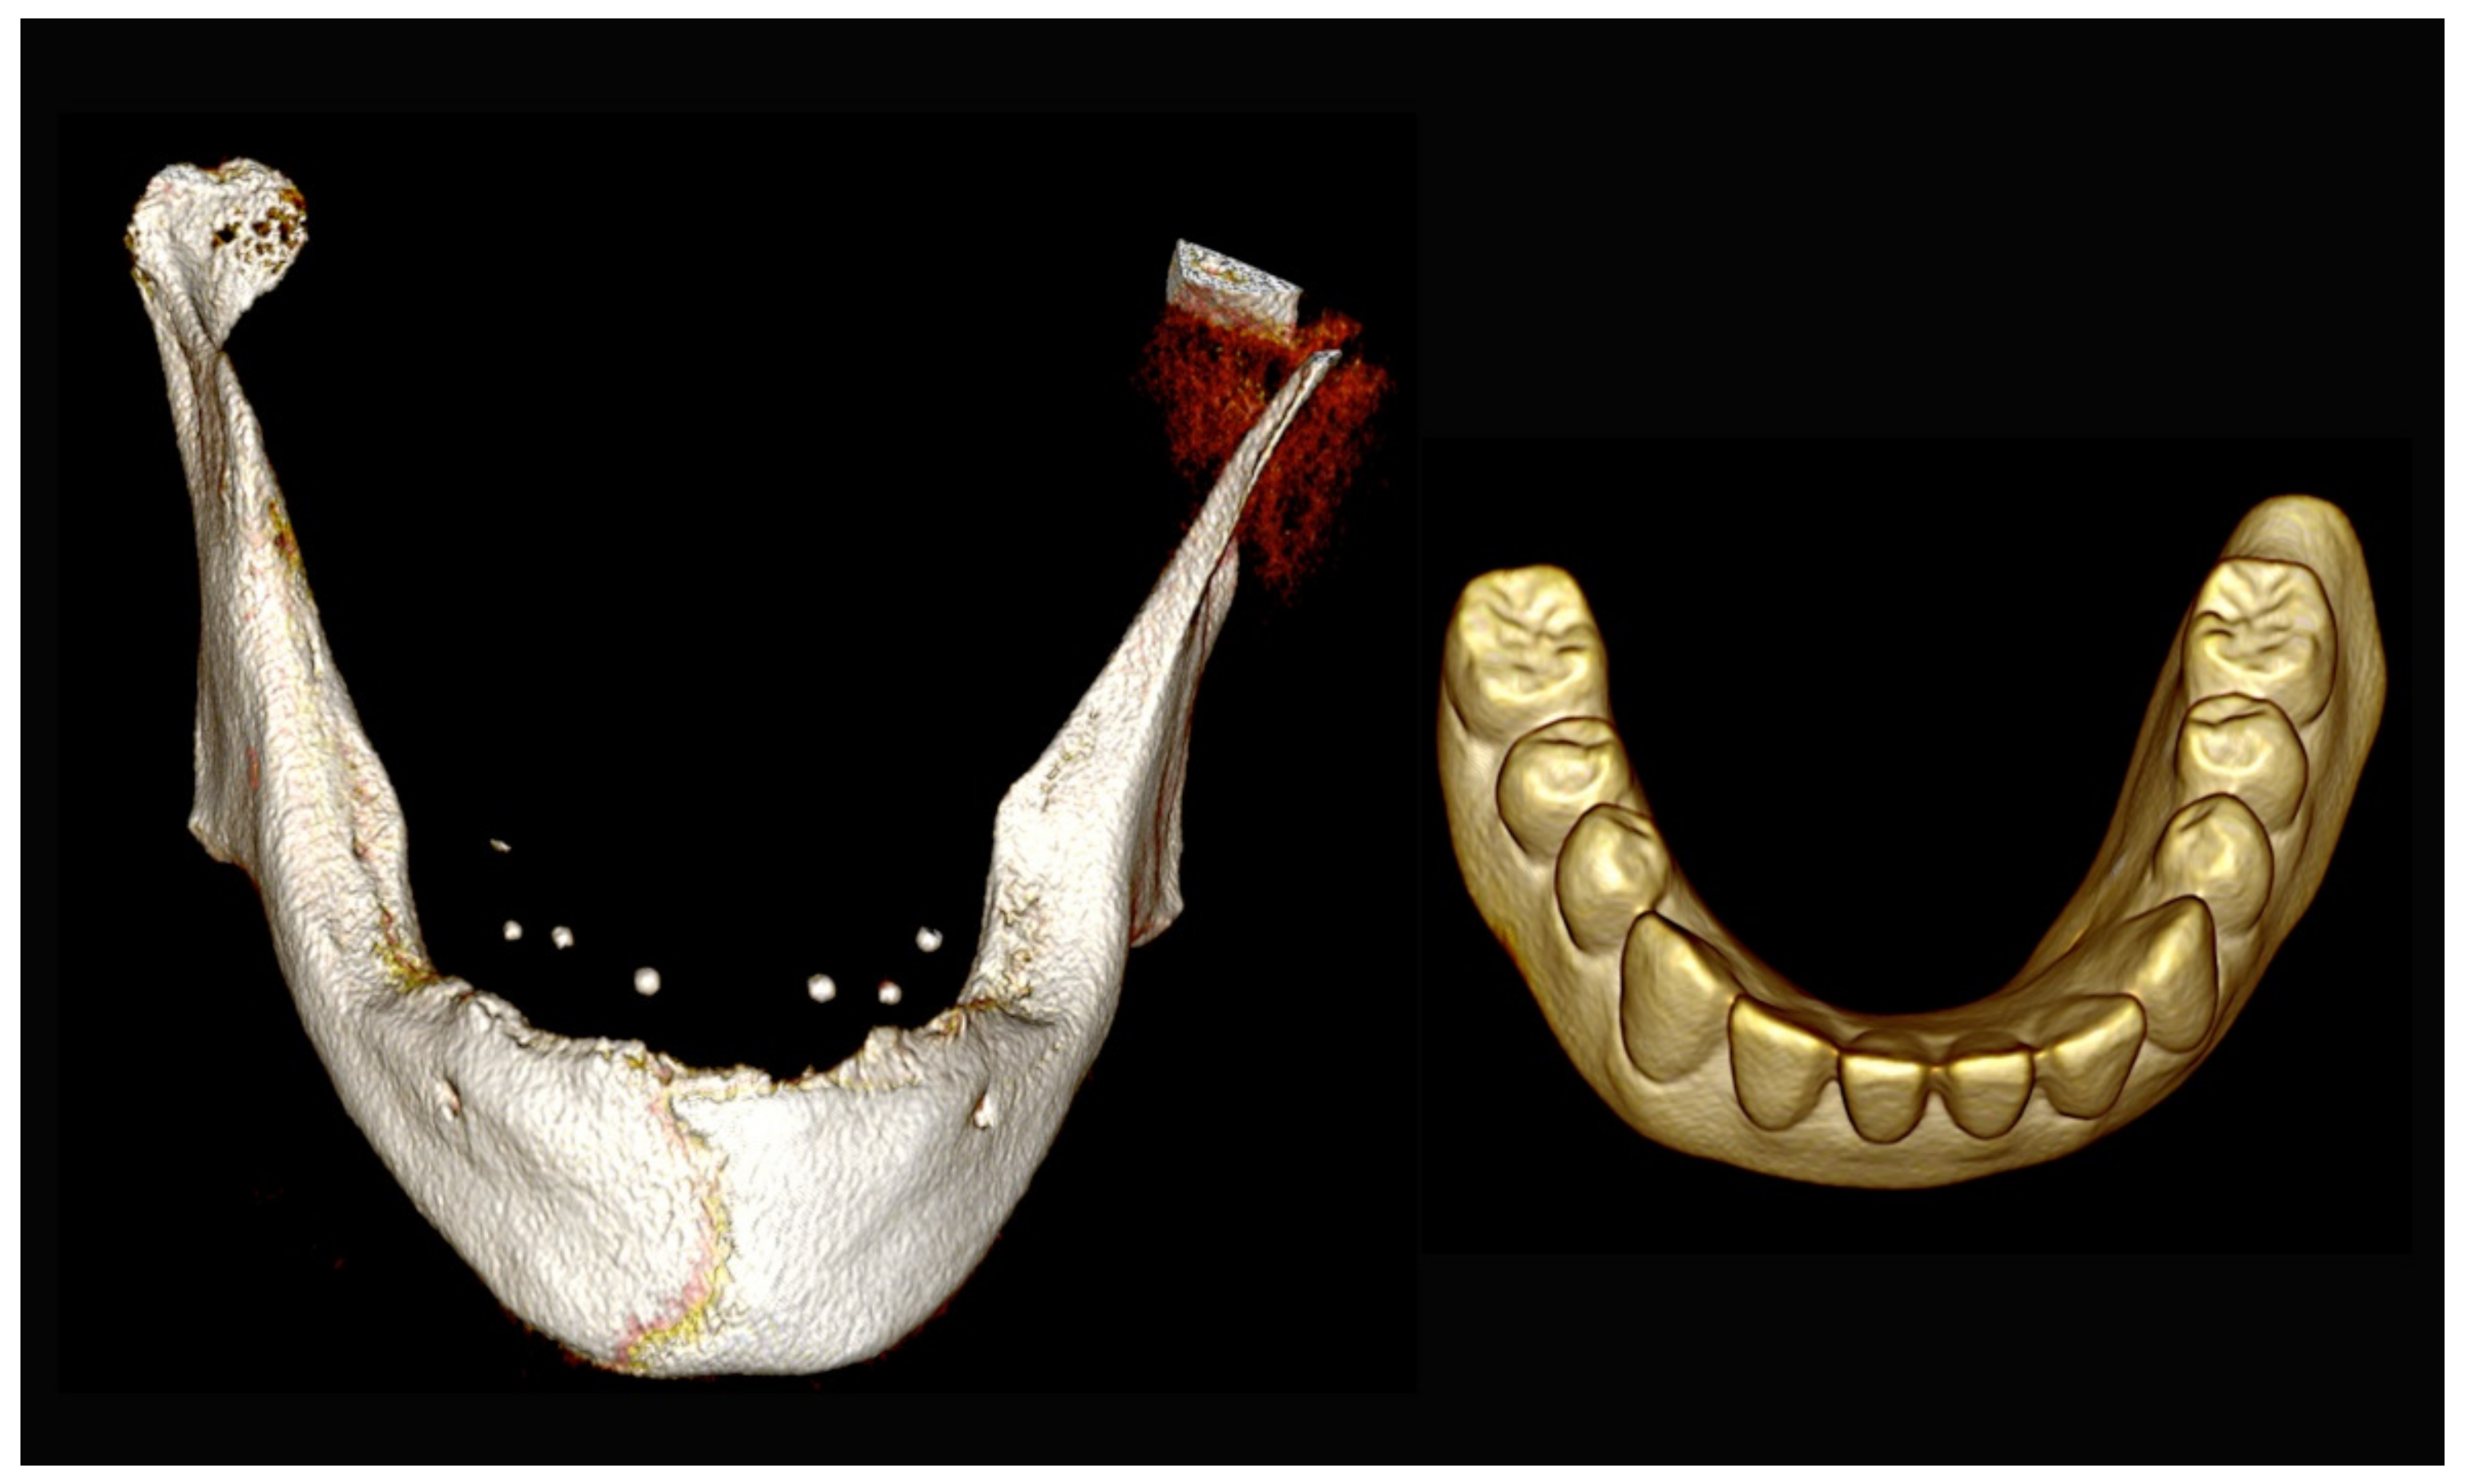

Figure 31.

Three-dimensional (3D) CBCT scan images of the edentulous mandible with the patient wearing the provisional prosthesis and 3D images of the prosthesis equipped with integrated radiopaque reference spheres scanned separately.